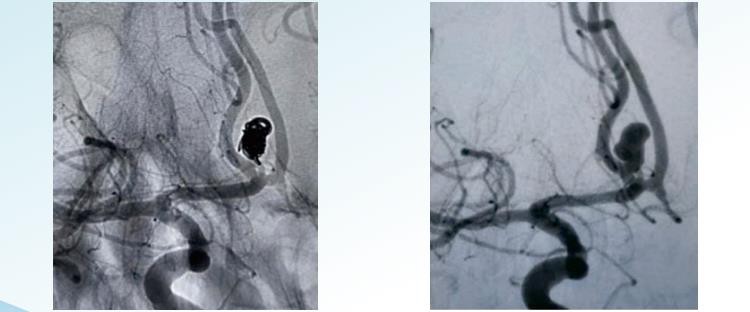

RenovaTM3D irrotettavat kelat

RenovaTMKierteiset irrotettavat kelat